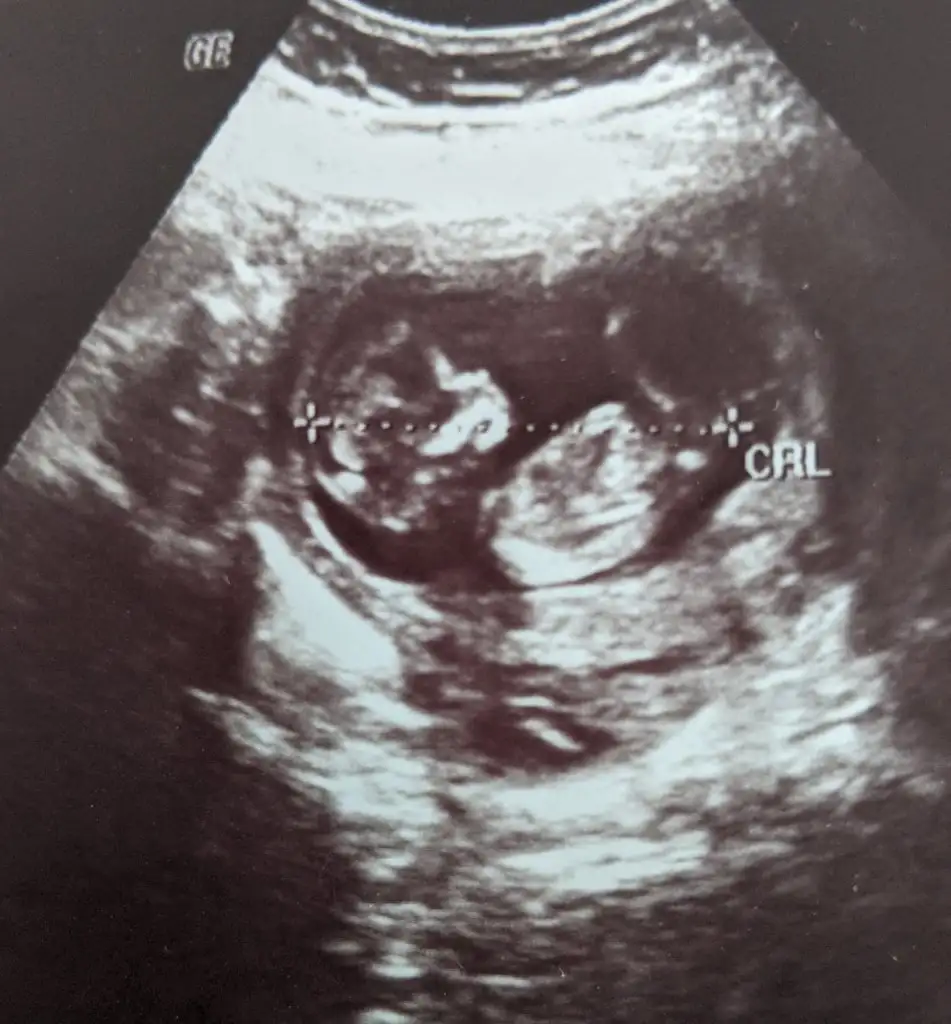

Eklentiler

• IMG_6134.webp

IMG_6134.webp

73,4 KB · Görüntüleme: 97